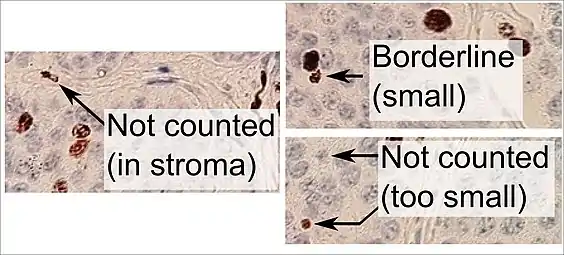

Ki-67 labelling index = 70% Counting positive versus negative nuclei with Ki-67 labeling, in this case in a neuroendocrine tumor of the small intestine. To count as positive, a nucleus should be at least half within the field of view, be large enough, and not be located in the stroma. Otherwise, even weakly positive nuclei count as positive.

Counting positive versus negative nuclei with Ki-67 labeling, in this case in a neuroendocrine tumor of the small intestine. To count as positive, a nucleus should be at least half within the field of view, be large enough, and not be located in the stroma. Otherwise, even weakly positive nuclei count as positive.